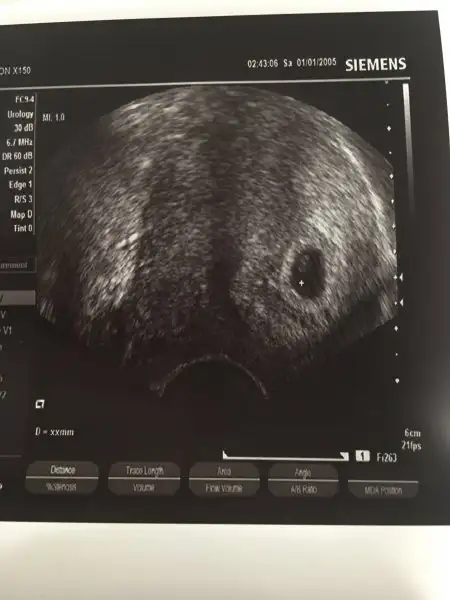

Kızlar kesemizi gördük bugün❤️2 kese görünüyor dedi doktor. Birinin içinde mercimek kadar belli, diğer kese flu dedi. Haftaya kadar gelişebilir de, tek gebeliğe dönebilir de dedi.

Gittik kuzumm. 2 kese görünüyor dedi doktor. Birinin içinde mercimek kadar belli, diğer kese flu dedi. Haftaya kadar gelişebilir de, tek gebeliğe dönebilir de dedi.